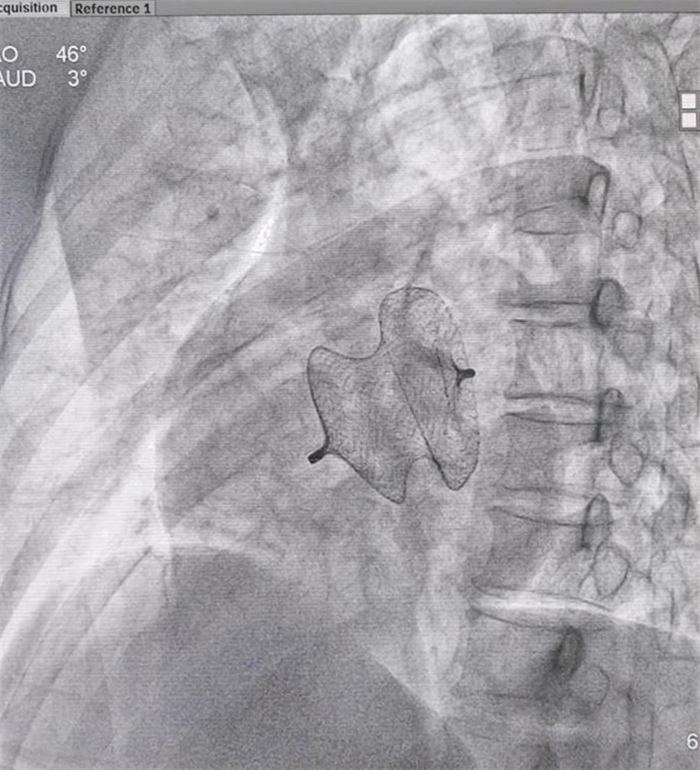

一名中年女性患者,因“间断心慌、气促、水肿1年加重1周,反复头晕”收治入院,诊断为先天性心脏病——房间隔缺损。经进一步详细检查心脏结构,确定了患者房缺最大直径约30mm,左向右分流。考虑到患者年龄,合并严重肺动脉高压等因素,经详细术前讨论认为患者可以采取经皮房间隔缺损封堵治疗方案。征得患者和家属同意后,7月26日为患者施行介入手术。

本次手术为微创手术,患者术后10小时即下床活动,患者及家属对手术结果非常满意。此介入手术避免了传统开胸、体外循环等高风险因素。